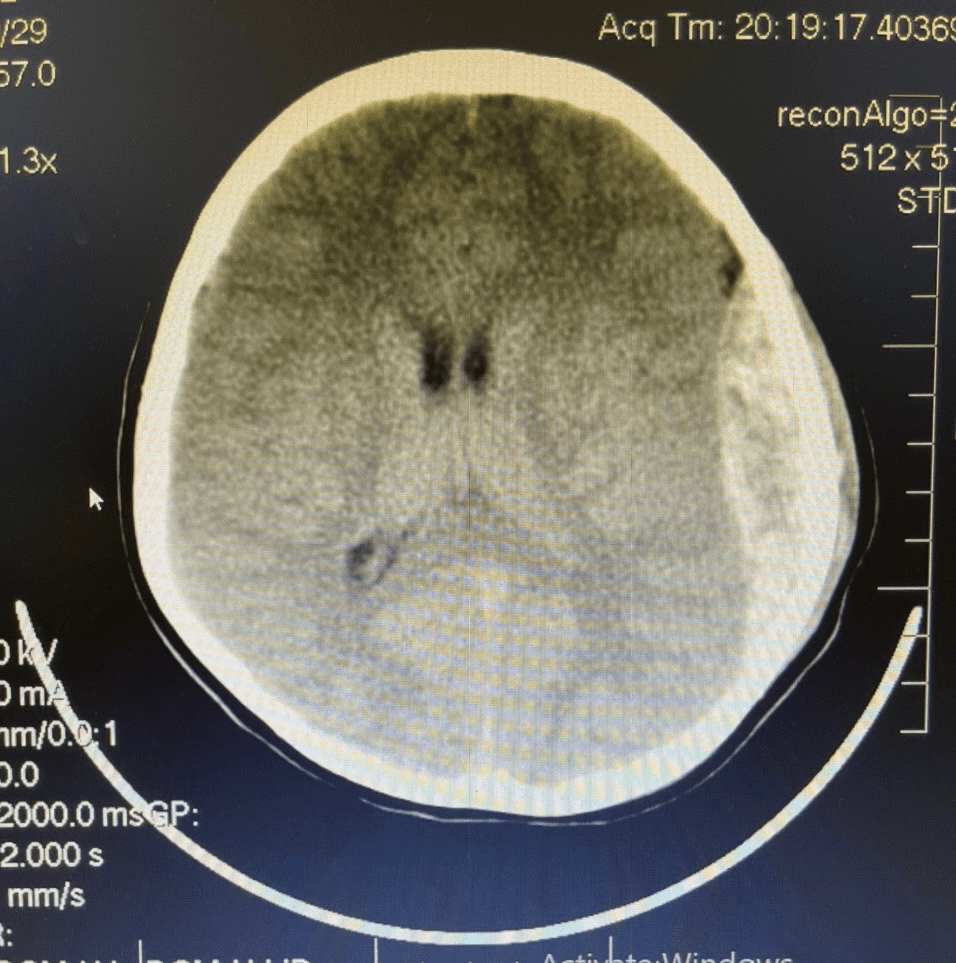

Hình ảnh chụp cắt lớp vi tính của bệnh trước và sau khi mổ chấn thương sọ não

Vào hồi 20h ngày 30/06/2022, Trung tâm y tế thành phố Móng Cái tiếp nhận trường hợp bệnh nhân là cháu N.V.G.B 8 tuổi (Hải Đông- Móng Cái). Trước khi vào viện, bệnh nhân đi xe đạp bị ngã xuống nền cứng, buồn nôn, nôn. Ngay sau khi tiếp nhận, thăm khám, chụp cắt lớp vi tính phát hiện hình ảnh tụ máu ngoài màng cứng, tình trạng tri giác giảm. Kíp trực đã báo cáo lãnh đạo, hội chẩn với bác sĩ chuyên khoa Bệnh viện đa khoa tỉnh, xác định bệnh nhân cần được mổ cấp cứu. Bệnh nhân khẩn trương được hoàn tất các xét nghiệm cận lâm sàng và được chỉ định mổ cấp cứu tại Trung tâm Y tế thành phố Móng Cái ngay trong đêm.